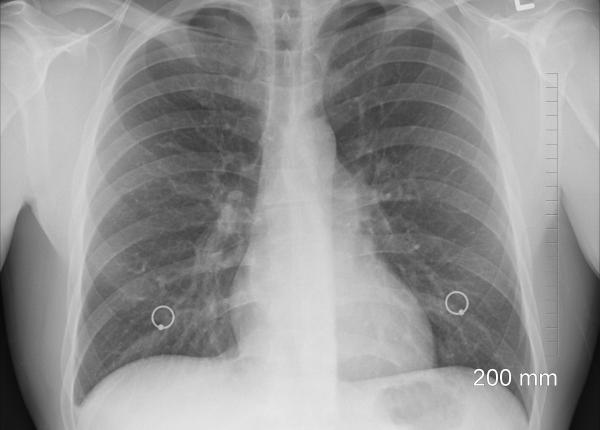

Pneumonia dată de coronavirus, cum afectează plămânii. Constatări făcute la CT